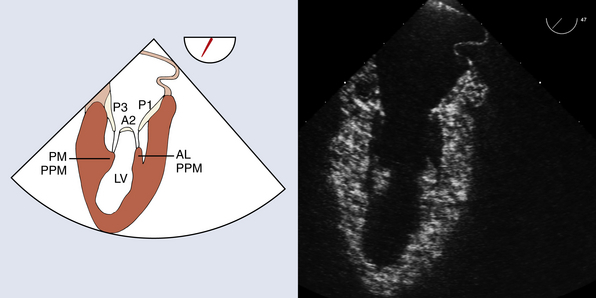

Label the Papillary muscles in the TG SAX Mid-Papillary TEE view

Label the Papillary muscles in the Mid Commissural View

Name the papillary muscles of the mitral valve.

1. Anterolateral

2. Posteromedial